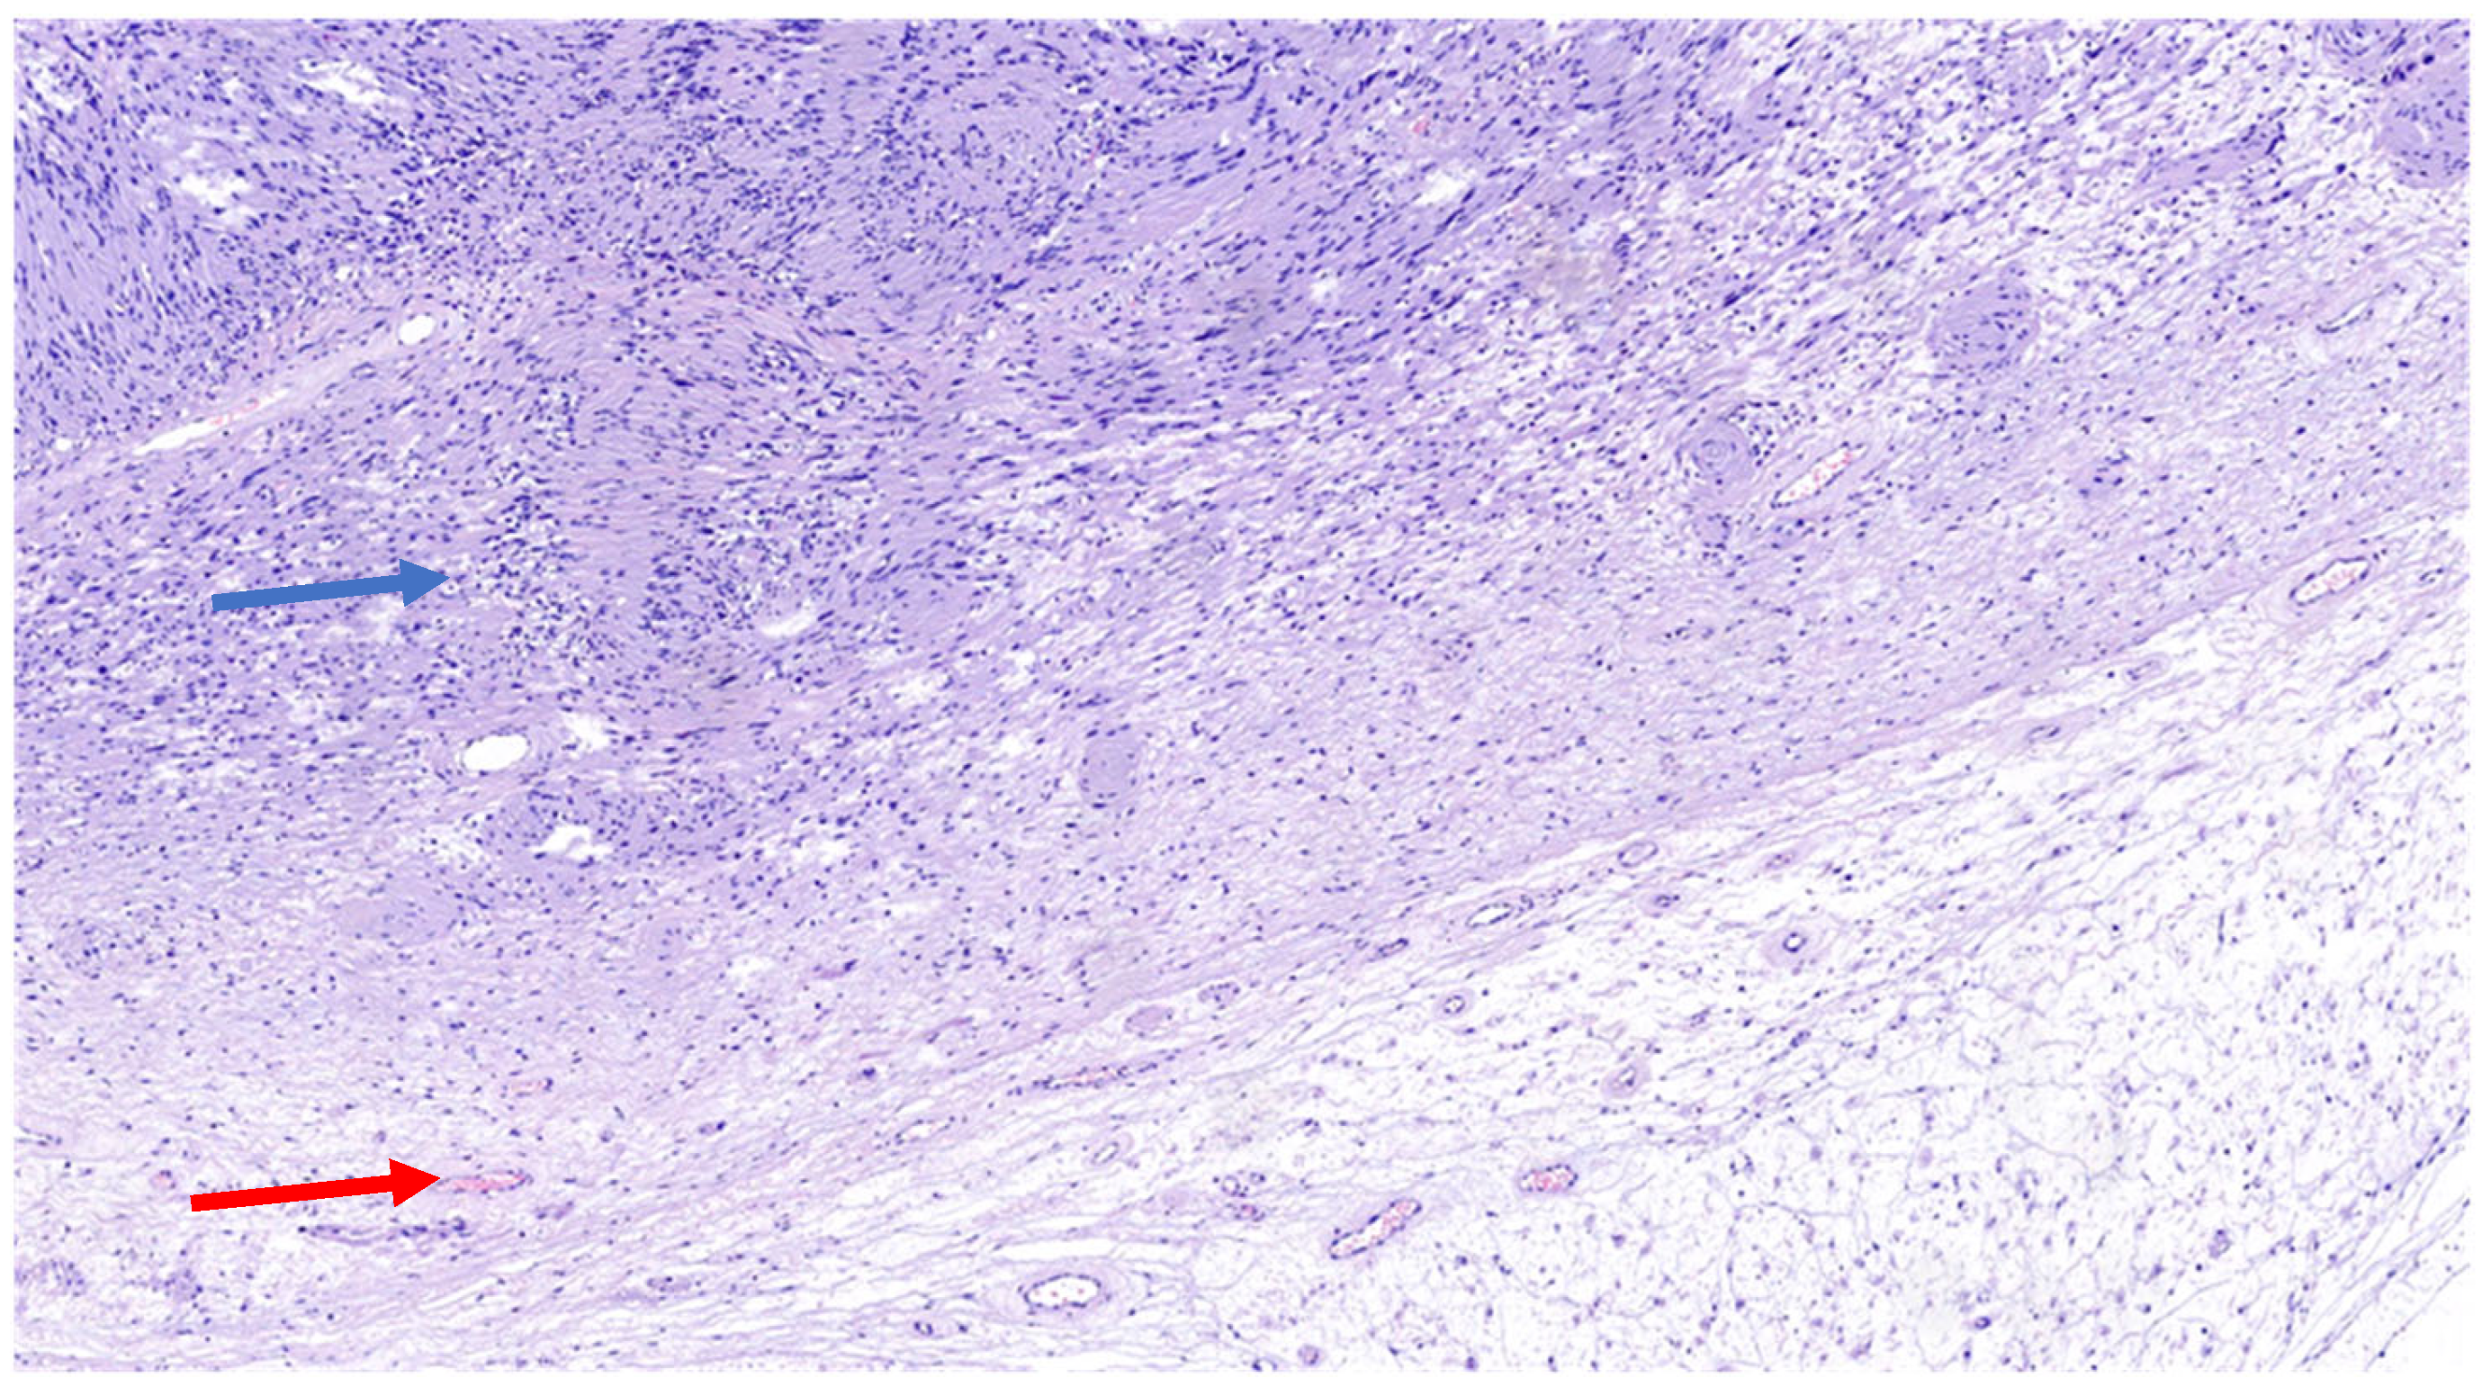

The schwannoma–perineurioma hybrid is the most reported subtype and typically occurs sporadically. Macroscopically, these tumors are well circumscribed but unencapsulated and are composed of spindle cells with wavy, tapering nuclei, eosinophilic cytoplasm, and indistinct cell borders. Histologically, they display a perineurioma-like pattern, with storiform, lamellar, or whorled growth, while still maintaining a schwannoma-like cytomorphology (Figure 3). Degenerative changes similar to those seen in ancient schwannomas, such as myxoid degeneration and cystic alterations, may also be present. Immunohistochemically, these tumors exhibit S100 and SOX10 immunoreactivity in schwannomatous areas, while perineuriomatous components express EMA, Claudin-1, and GLUT-1 (Figure 4). Unlike schwannoma–neurofibroma hybrids, these tumors are usually sporadic and not strongly associated with genetic syndromes. They are considered benign with an extremely low recurrence risk, although rare cases of low-grade malignant potential have been reported in the literature [5]. It has also been reported that the majority of hybrid schwannoma–perineuriomas harbor VGLL3 rearrangements [28,29].

Figure 3. H&E (100× magnification) of a peripheral nerve sheath tumor with features of schwannoma and perineurioma. The schwannomatous component: areas of spindle-shaped cells arranged in bundles, with Verocay bodies (blue arrow), moderate cellularity. The perineurial component: uniform spindle cells arranged in a storiform pattern within a denser collagenous matrix (red arrow).